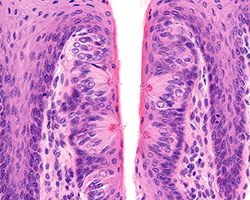

Digestivo II. Tubo

Digestivo II. Tubo

Esófago, estómago, intestino delgado y grueso y apéndice.

(19 preparaciones) -